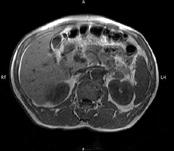

问题 男,52岁,下肢无力伴多饮多尿2 年余,实验室检查:低血钾,血醛固酮水平及24h 尿醛固酮定量超过正常值,MRI检查如图所示,应诊断为 ( )

选项 A、左肾上腺髓脂瘤 B、左肾上腺转移瘤 C、左肾上腺腺瘤 D、左肾上腺嗜铬细胞瘤 E、左肾上腺囊肿

答案 C